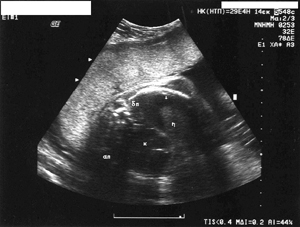

Εικόνα 2. Συλλογή υγρού στις

πλευροδιαφραγματικές ζώνες του θώρακα και υγρό στο περικάρδιο. (η=ήπαρ, κ=καρδιά,

Δπ=δεξιός πνεύμονας, Απ=αριστερός πνεύμονας)

Ο υπερηχογραφικός έλεγχος του εμβρύου απέδειξε επιπλέον του ύδρωπα και υποπλαστικούς

νεφρούς (εικόνα 2), ολιγάμνιο, και χαμηλό βιοφυσικό προφίλ (BPS=7). Πραγματοποιήθηκε